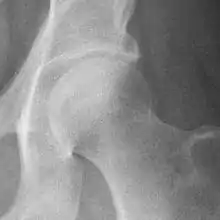

Hip

The most commonly used radiographic classification system for osteoarthritis of the hip joint is the Kellgren–Lawrence system (or KL system).[6] It uses plain radiographs.

| Grade | Description |

|---|---|

| 0 | No radiographic features of osteoarthritis |

| 1 | Possible joint space narrowing (normal joint space is at least 2 mm at the superior acetabulum)[7] and osteophyte formation |

| 2 | Definite osteophyte formation with possible joint space narrowing |

| 3 | Multiple osteophytes, definite joint space narrowing, sclerosis and possible bony deformity |

| 4 | Large osteophytes, marked joint space narrowing, severe sclerosis and definite bony deformity |

Osteoarthritis of the hip joint may also be graded by Tönnis classification. There is no consensus whether it is more or less reliable than the Kellgren-Lawrence system.[8]